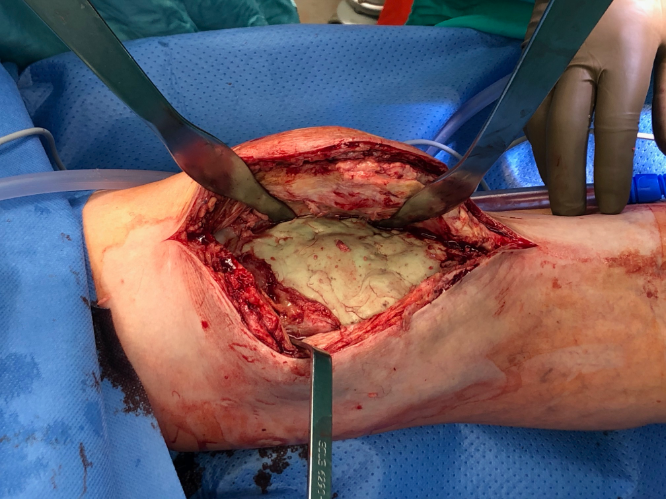

In the appropriate position and verification of the stability of the rod arthrodesis 80−120 g of hand-mixed AB bone cement (as revision cement with gentamicin and clindamycin if indicated) are inserted into the joint cavity and shaped both around the AO rods and the clamp (Fig. 6.).

Vancomycin may be added, depending on the pathogen spectrum. Since the long-term stability of the bone cement is immaterial during the interim phase of 4−8 weeks, a higher admixture of antibiotic (>10%) can be considered. In any case, a sufficient cement volume should be used for the filling of the joint cavity that permits wound closure during reimplantation without tension despite the expected capsular shrinkage with the static spacer. This is probably also the basis for better mobility compared to other static spacers. However, it is crucial that excessive penetration of cement into the bone of the femur and tibia metaphysis are avoided. The subsequent removal of the cement with indwelling fixed rods may be difficult under these circumstances and cause additional bone loss. This can also be prevented by a time-delayed insertion of the AB cement with a doughy consistency. Should it be impossible to remove the connection clamp in extreme cases, the hollow rods can be cut with a conventional bolt cutter. It is also crucial that dorsal leaking of cement by strong cement compression is avoided in case of capsule defects to reduce the risk of vascular/nerve compression.

The capsule suture should be without tension and sealed despite generous cement application in the ventral joint portion; that means the capsule expansion that is usually present due to effusion should be preserved initially. During the hardening the capsule adaptation can be carefully simulated and excess cement can be removed if necessary.